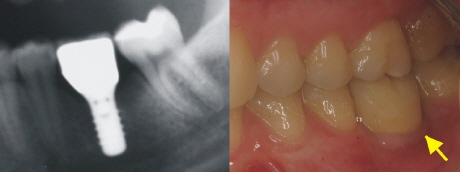

Das Röntgenbild links zeigt den perfekten Sitz der Implantatkrone. Die Lücke ist ohne weitere Schäden an Nachbarzähnen stabil versorgt. Für den Patienten ist die Implantatkrone nun gar nicht mehr zu erkennen und der Zahn im Ganzen nach dem Vorbild der Natur wiederhergestellt.

Der gelbe Pfeil zeigt auf dem Bild rechts, wo sich die Implantatkrone in der Zahnreihe „versteckt“.